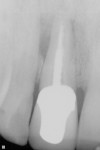

A 39-year-old nonsmoking male presented with a failing endodontically treated, fractured maxillary right central incisor. A draining sinus track was noticed at the mucogingival junction distal to the right central incisor (Figure 10). A pretreatment periapical radiograph demonstrated the large alveolar defect distal-apically (Figure 11). Clinically, the site registered a 12-mm probing depth at the distal line angle of the right central incisor. Following the technique previously outlined by the author, a preoperative administration of moxicillin and clavulanate potassium 875 mg 20 1 q 12 hours was started 1 day before the procedure. The patient was given the appropriate local anesthetic, the tooth removed, and the extraction site debrided by mechanical (curettage) and rotary instrumentation using high-speed handpiece with a round No. 6 diamond until all remnants of the periodontal ligament and granulation tissue were removed. A Tapered Screw Vent® implant (Zimmer Biomet Dental, zimmerbiometdental.com) measuring 4.7 mm x 13 mm was placed to the appropriate depth and achieved initial stabilization in the alveolar bone apical to the extraction site. An allogenic, mineralized cancellous, 1-mm to 2-mm-particle-size graft (Tutogen Medical GmbH, rtix.com) was placed into the remaining peri-implant defect, and condensed to completely fill the osseous defects and void in the preexisting buccal plate (Figure 12). A plastic provisional abutment was seated, and the preexisting full-coverage porcelain restoration was retrofitted to the plastic provisional abutment and served as the immediate provisional restoration. After a 3-month healing and maturation phase of the implant placed, the graft was inserted and the tissue was sculpted and held in place by the immediate provisional restoration, which allowed for a stable, mature soft-tissue emergence profile. The restorative clinician completed the final implant abutment and crown for the right central incisor. The patient followed regularly scheduled implant maintenance visits biannually. Figure 13 shows the 15-year post-treatment clinical view, and a 15-year post-treatment clinical view can be seen in Figure 14.